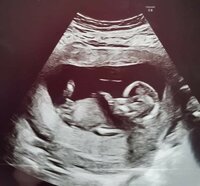

Noniin ultra ohi ja kaikki oli just niinku pitääkin riskiluku oli pieni 1:70000. Rakenneultra varattiin mun mielestä aika myöhälle kun se on vasta rv 21+5